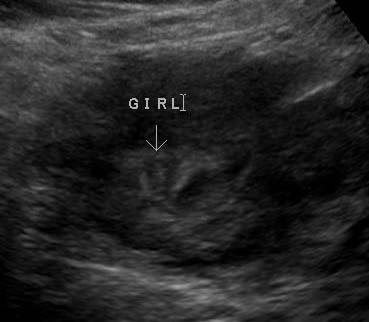

هذي ياقلبي صورة جنين عمره 19 اسبوع (بنوته)